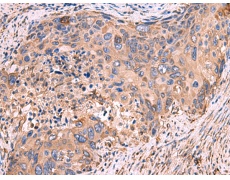

IHC positive control:

Human cervical cancer

IHC Recommend dilution:

40-200